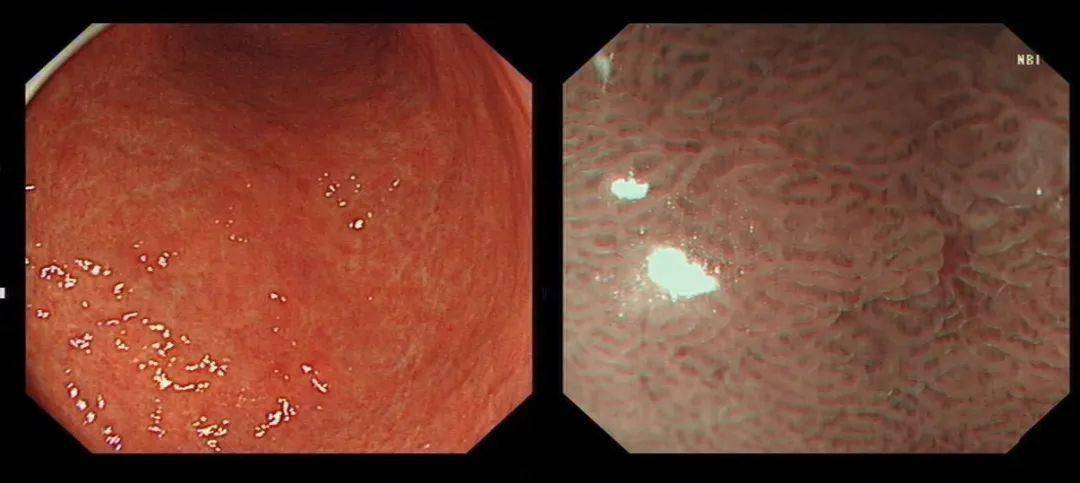

慢性萎缩性胃炎图片

慢性萎缩性胃炎图片,慢性萎缩性胃炎c2

慢性萎缩性胃炎胃镜

慢性萎缩性胃炎镜下

萎缩性胃炎胃镜图

慢性萎缩性胃炎胃镜图